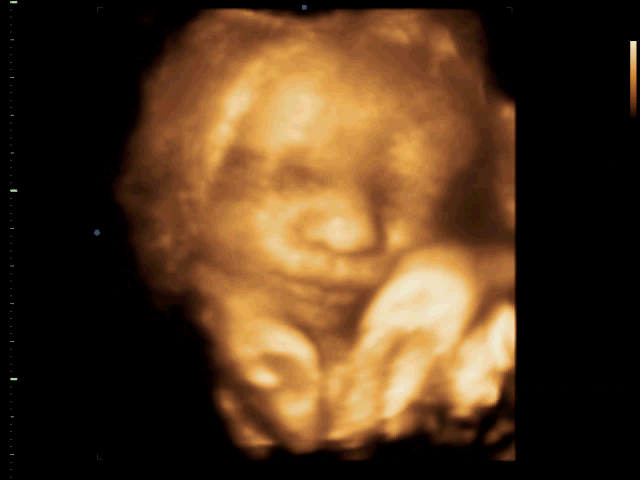

to nansie: Mám fotečky z každé kontroly, i z poslední, je fakt rozkošnej, už aby byl na světě

No to je fešák

. Na první za slušňáka a na tý druhý se krásně kření